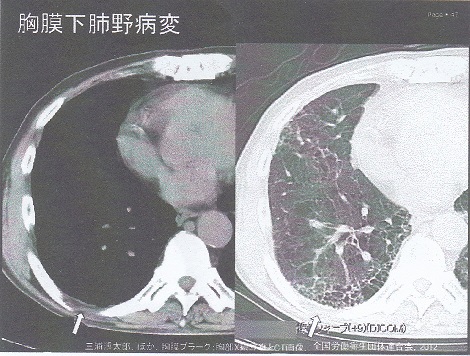

石綿による胸膜プラークと鑑別が必要な病態としては以下のものがある。

④ 肋間静脈

⑤ 胸膜直下肺野病変

https://www.rofuku.go.jp/Portals/0/data0/sanpo/kadai/pdf_slide/h18/h18slide_hyogo.pdf

胸膜プラークの検出率は、単純レントゲンでは35%程度であること、CTも撮影条件によっては1/3程度描出できない点注意が必要である。